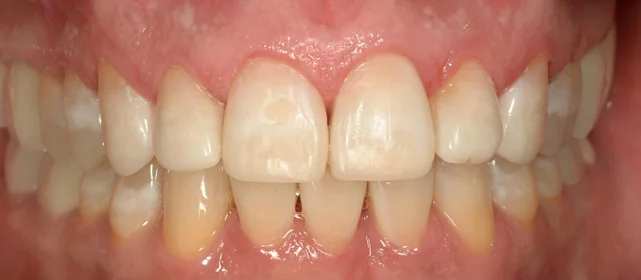

Нарушение соотношения челюстей и неправильное положение зубов — зубные ряды смыкались некорректно, зубы стояли со смещением.

Зубы выровнены, смыкание нормализовано. Установлены несъёмные ретейнеры на обе челюсти, сняты сканы для ретенционных кап. Консультация ортопеда запланирована на более поздний срок.

Проблема: Пациентку беспокоило неправильное смыкание зубов и их положение — ряды не сходились как нужно, зубы стояли со смещением. Это влияло и на внешний вид, и на то, как распределялась нагрузка при жевании.

Решение: Поставили прозрачные элайнеры 3D Smile на обе челюсти. Начали с набора из 34 кап, но в процессе стало понятно, что для полной коррекции нужна доработка — заказали дополнительный набор из 28 кап. Это нормальная ситуация: организм реагирует на перемещение зубов индивидуально, и заранее предсказать точное количество кап до последней штуки невозможно. В итоге 62 капы за 32 месяца — зубы встали на место, смыкание пришло в норму. Параллельно следили за гигиеной, чтобы дёсны оставались здоровыми на протяжении всего лечения.

Основной набор из 34 кап выполнил бо́льшую часть работы, но для финальной коррекции смыкания понадобился дополнительный комплект. Это не редкость — зубы двигаются с разной скоростью, и последние доли миллиметра часто требуют доработки. В итоге получили стабильный результат, который зафиксировали ретейнерами.